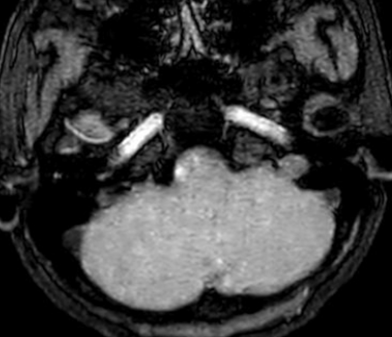

Cộng hưởng từ sọ não: Không phát hiện tổn thương bất thường.

Hình 5: Không phát hiện hình ảnh bất thường trên phim cộng hưởng từ sọ não.